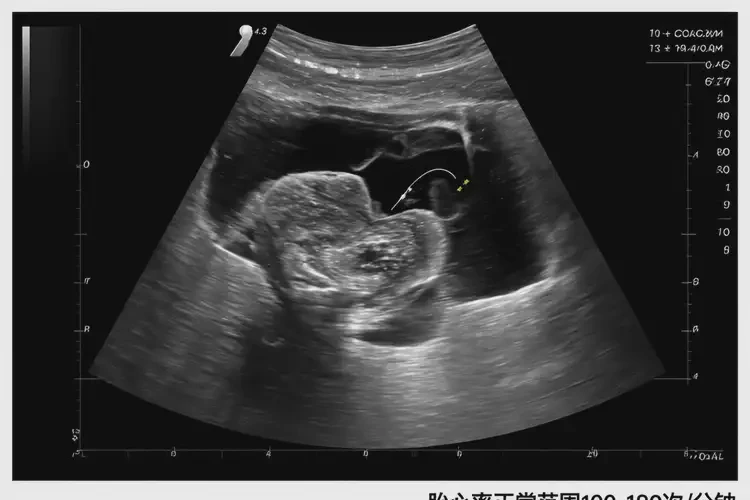

懷孕第9周胎心70左右有危險(xiǎn)嗎(圖1)

懷孕第9周胎心70左右有危險(xiǎn)嗎

胎心率在懷孕第9周約為70次/分鐘可能存在風(fēng)險(xiǎn)。胎心率是評(píng)估胎兒健康狀況的重要指標(biāo),正常情況下,胎心率在懷孕早期(約6-10周)通常在100-180次/分鐘之間波動(dòng)。如果胎心率持續(xù)低于100次/分鐘,可能提示胎兒存在潛在的健康問(wèn)題,如胎兒宮內(nèi)窘迫、先天性心臟病等。